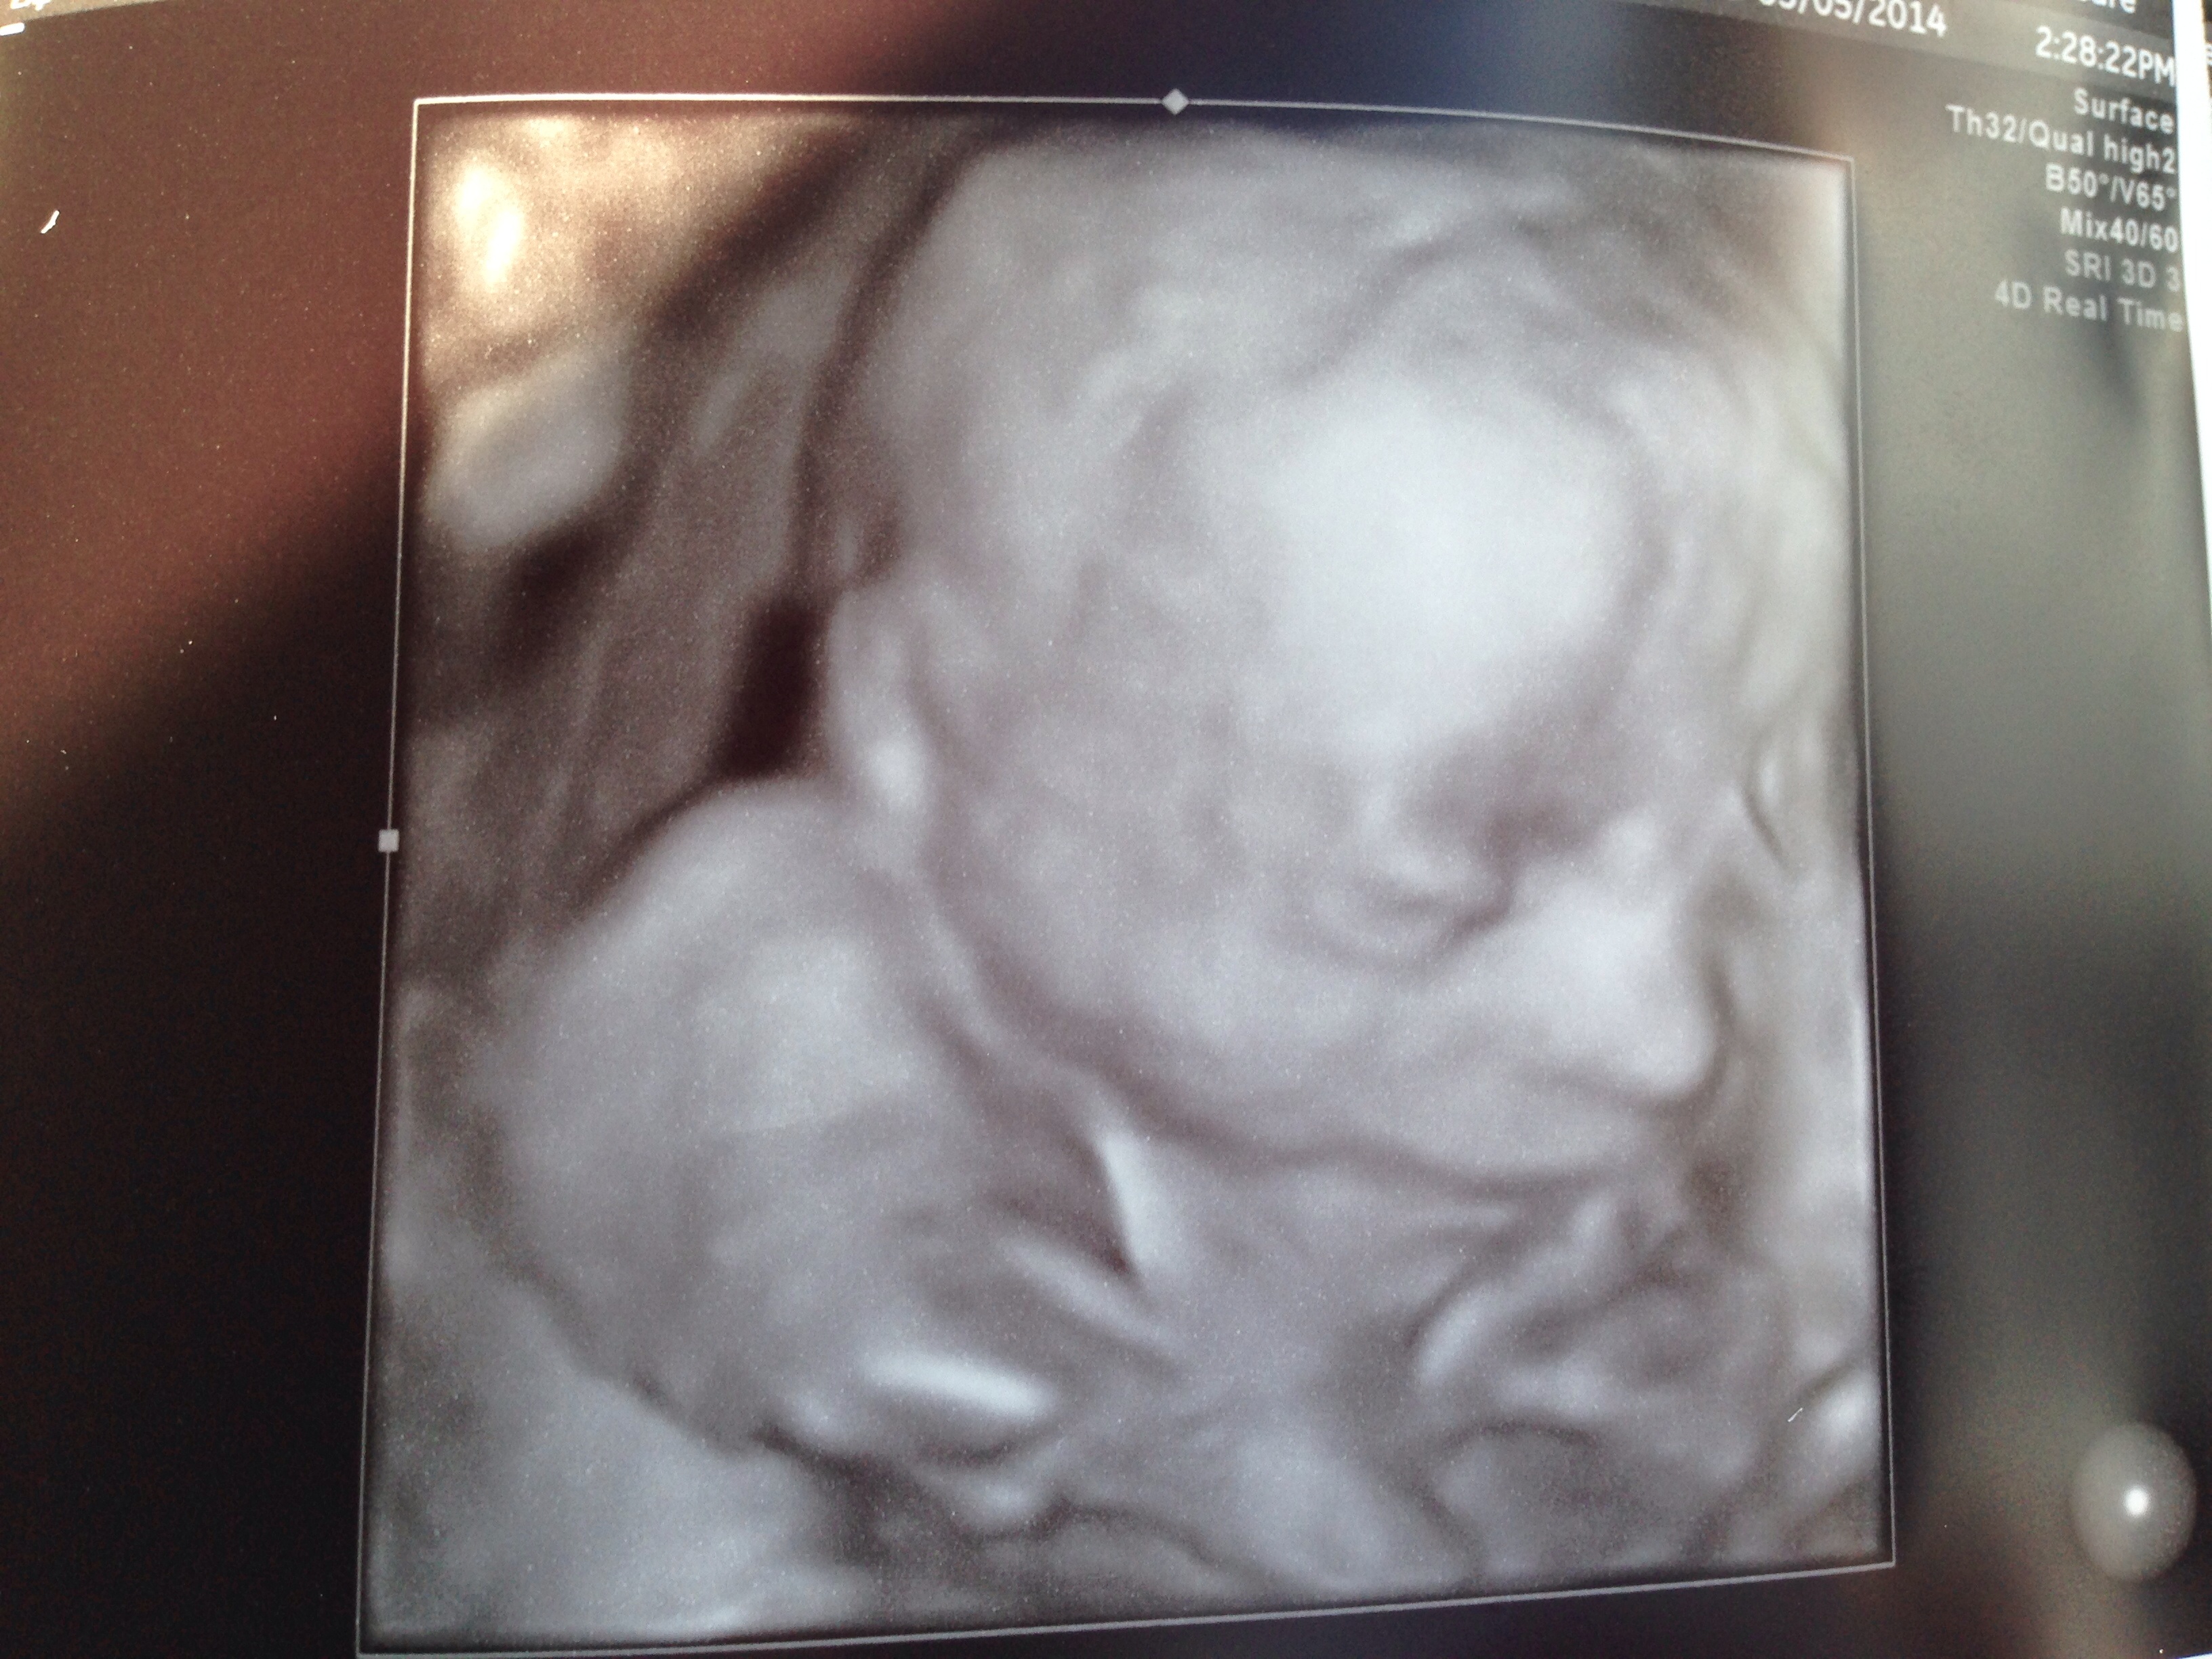

Good news is that my baby girl is perfect in every way. She's breech, had her head down, hands in front of face, feet over her head, but we did manage to get a couple of good shots:

imageimage